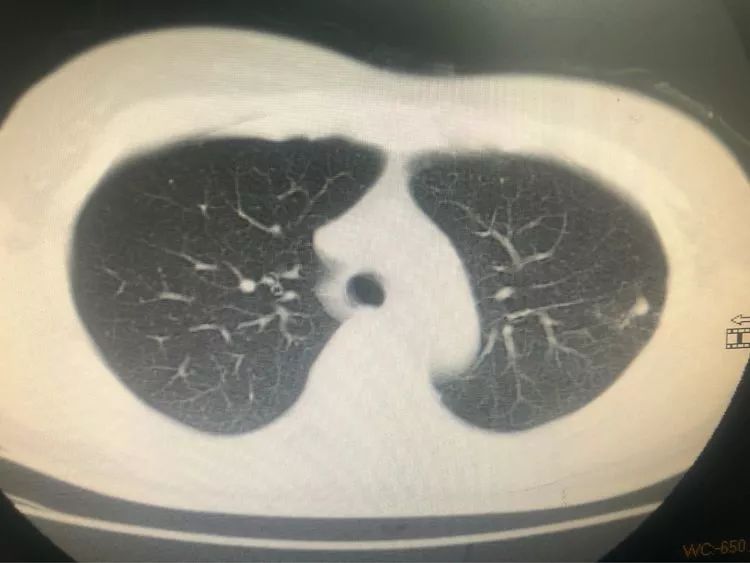

第二例 46歲的劉阿姨既往有肺結核病史,規(guī)則治療,三月前出現(xiàn)胸背部隱痛,在其他醫(yī)院胸片檢查考慮陳舊性結核,但她一直未在意,之后由于癥狀一直沒有緩解便選擇來省胸科醫(yī)院就診,經(jīng)檢查,胸部CT兩上肺確實有陳舊性病兆,但左下背段有一個1.5厘米左右的結節(jié)。

像這種肺外周的結節(jié)一般的氣管鏡做不到,所以醫(yī)生選擇使用穿刺活檢。

穿刺活檢后送至病理科,待報告出來后顯示腺癌,可惜,癌細胞已經(jīng)向肋骨和胸椎多處轉移,患者已經(jīng)失去了手術機會。